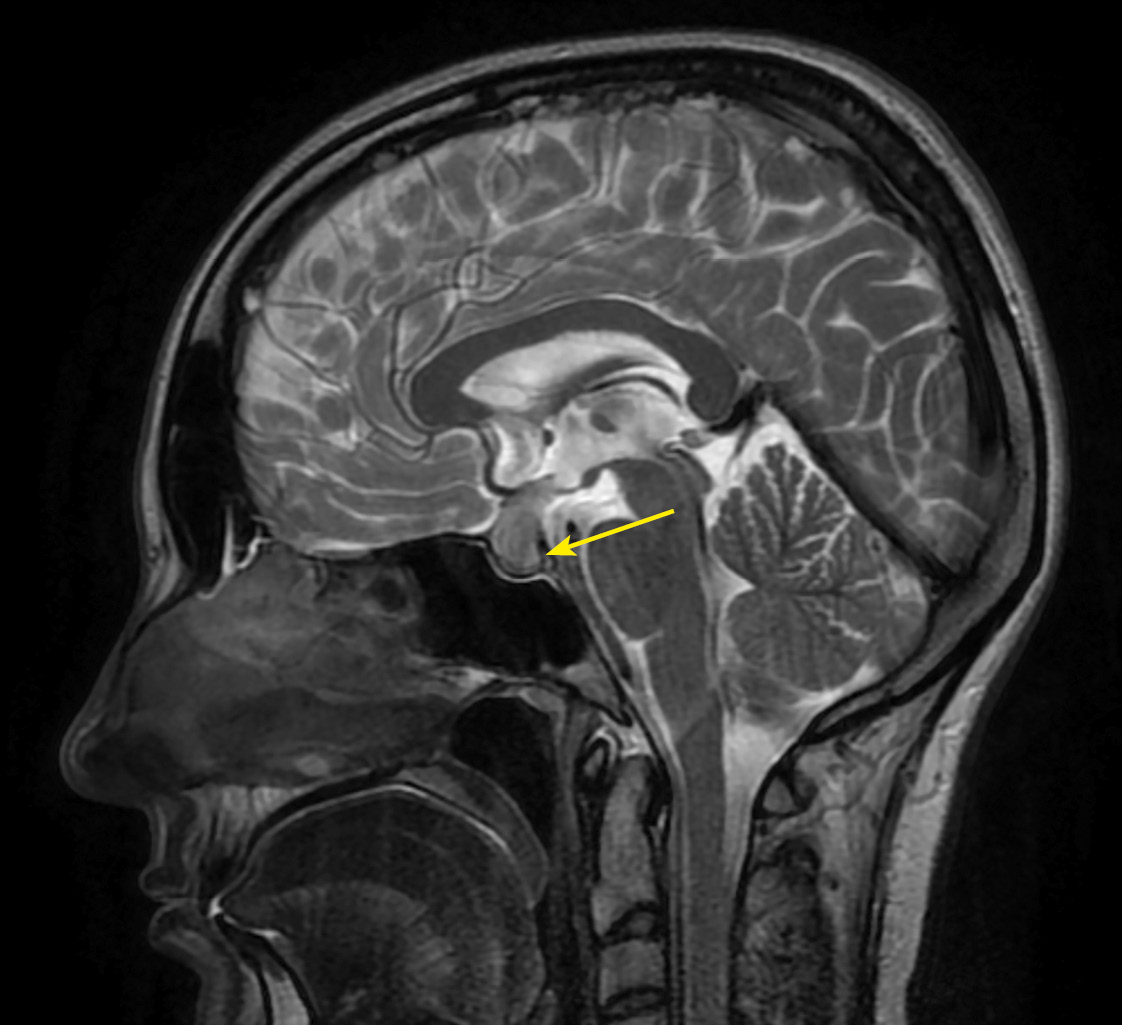

На фоне продолжающейся терапии дексаметазоном, по данным МРТ головного мозга, отмечался регресс изменений хиазмально-селлярной области с утолщением воронки гипофиза, отсутствием сигнала от нейрогипофиза (рис. 3, 4).

Рисунок 4. МРТ головы без контрастного усиления, Т1-взвешенное изображение,

сагиттальная проекция. Нейрогипофиз не дифференцируется (изменения указаны стрелкой).